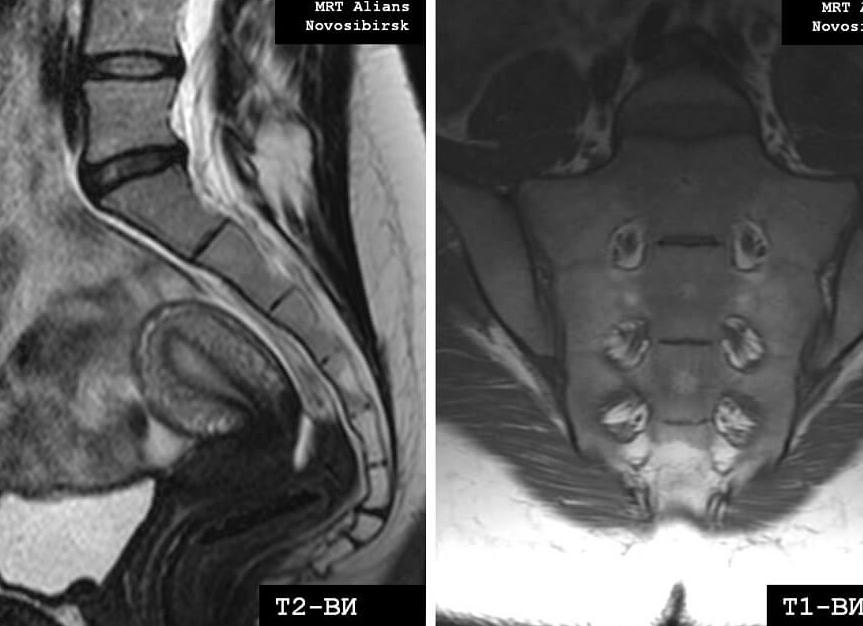

Пример МРТ-снимка крестцово-копчикового отдела